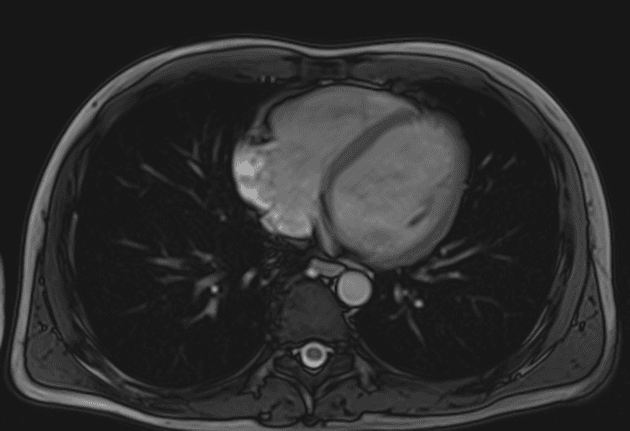

Bệnh nhân đã biết mắc bệnh Crohn, đến làm cộng hưởng từ ruột (MR enterography). Phát hiện tình cờ.

Biến dạng cấu trúc (architectural distortion) ruột kèm các đoạn hẹp (strictures) và các đường rò (fistulae) tại hố chậu phải, liên quan đến hồi cuối (terminal ileum). Cụ thể, phát hiện nhiều đường rò hồi – hồi (ileo-ileal) và hồi – đại tràng (ileocolonic), liên quan đến đại tràng lên và đại tràng xích-ma (sigmoid colon).

Cộng hưởng từ ruột (MRI enterography) phải dừng sớm khi phát hiện hình cản quang kim loại tại vùng chậu giữa và hố chậu trái.

Ngay khi phát hiện hình cản quang kim loại, MRI đã được dừng lại.

Các ống nội soi dạng viên nang không tương thích với MRI, do đó MRI chống chỉ định trong các trường hợp này.

Hình ảnh học xác nhận bệnh Crohn thể biến chứng với các hình ảnh: biến dạng cấu trúc (distortion), giãn đoạn trước hẹp (prestenotic dilatation) tại hồi tràng giữa đến cuối, và nhiều đường rò ruột – ruột (entero-enteric), ruột – đại tràng (entero-colonic), kèm theo các đoạn hẹp (strictures).